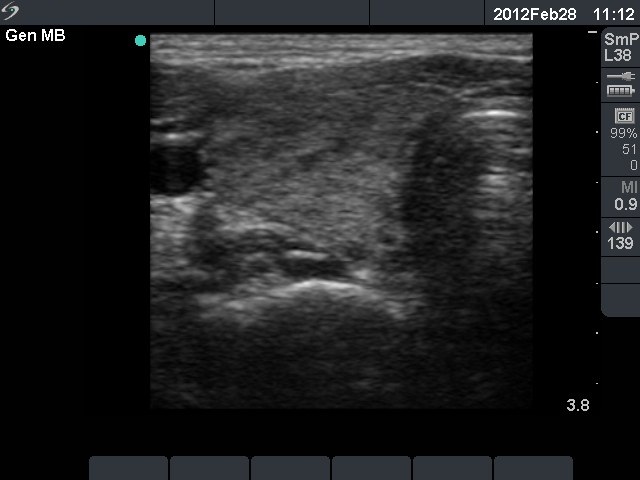

Initial investigation 5 months after delivery (1st and 2nd rows of images)

Clinical presentation: a 24-year-old woman was referred for an evaluation of weight loss. She had a delivery 5 months before the present examination.

Palpation: no abnormality.

Functional state: moderate degree of hypothyroidism with TSH 0.01 mIU/L, FT4 30.8 pM/L. TRAK 1.6 U/L (normal value below 1.5), aTPO 1 U/mL.

Ultrasonography: the thyroids were echonormal. The echogenicity index was around 15%. There was no nodule. The vascularization was average.Cytology resulted in Hashimoto's thyroiditis.

Clinical diagnosis: hyperthyroidism. Post partum thyroiditis.